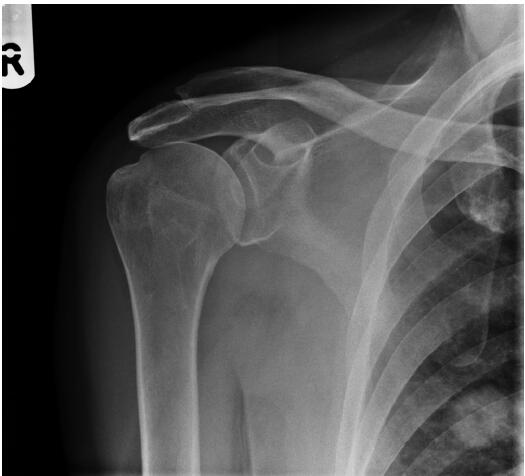

患者,男性,62歲,跌倒后,肩膀越來(lái)越疼。全科醫(yī)生要求該患者進(jìn)行放射檢查(圖1)。

圖1右肩前位X光平片

僅根據(jù)影像學(xué)檢查,需要的下一步檢查是什么?